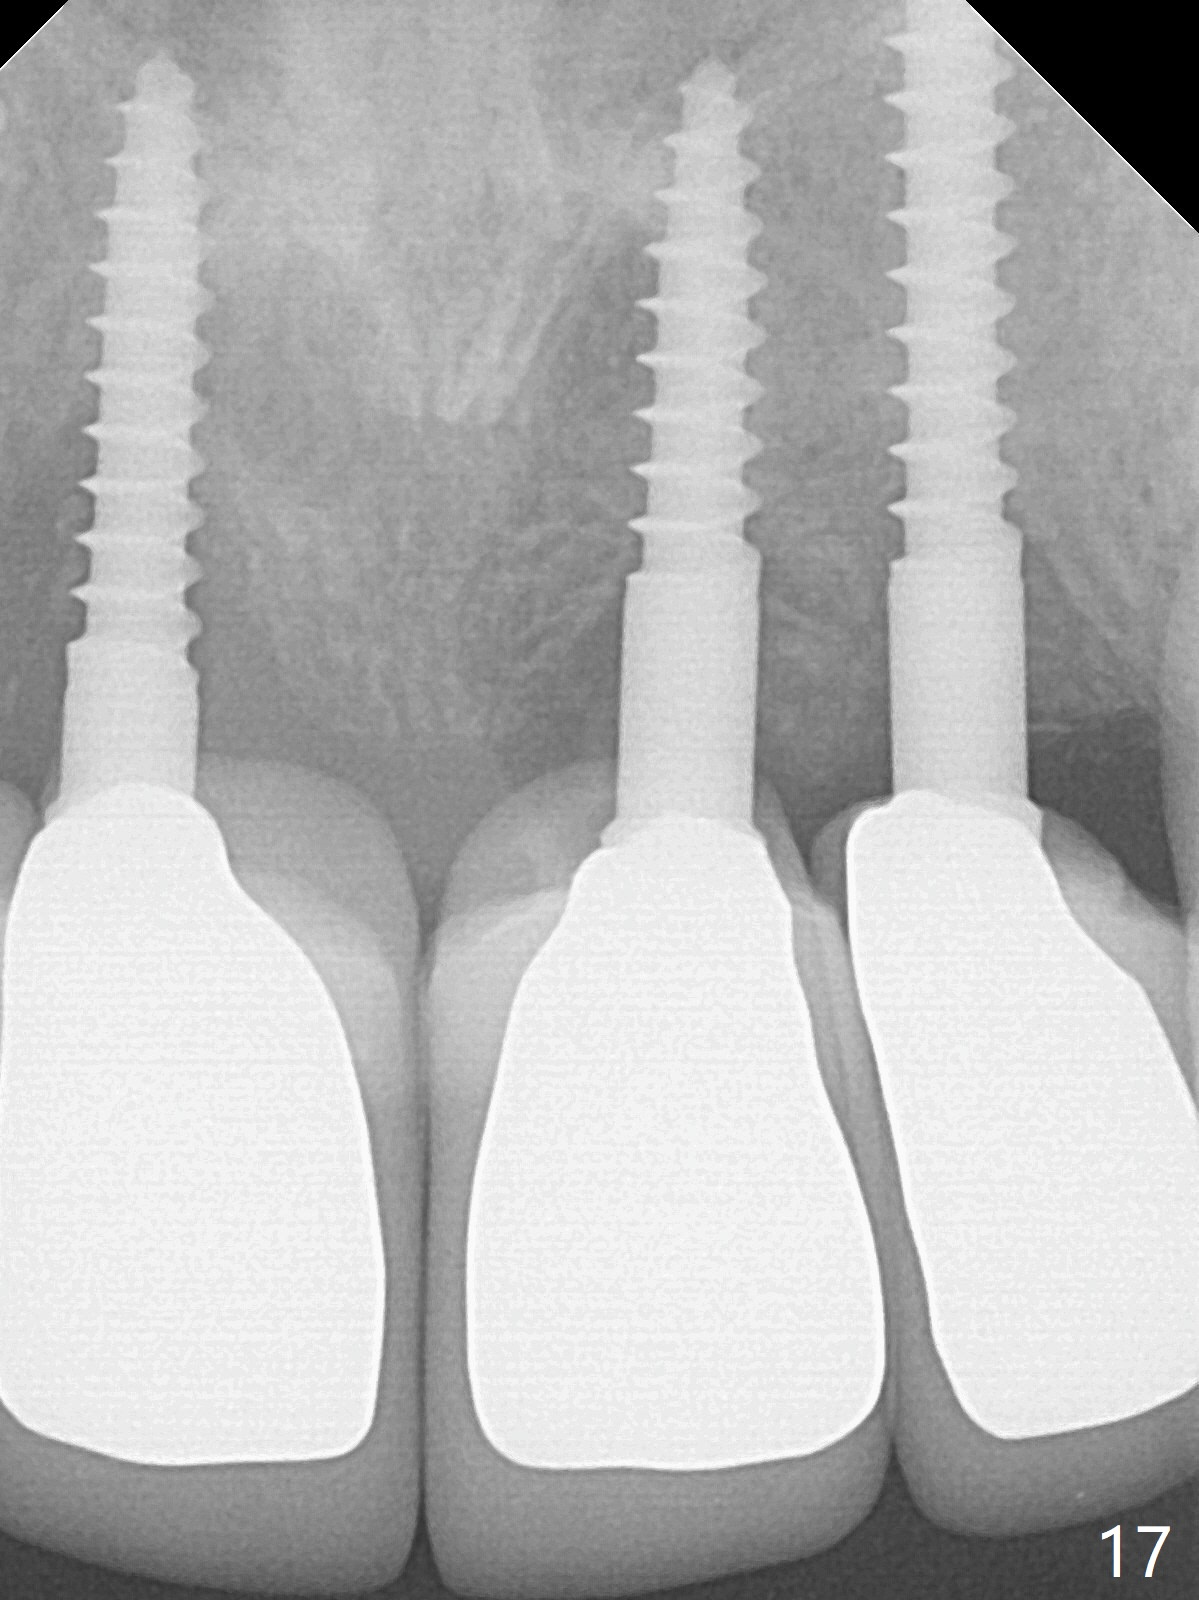

Although the ridge of the maxillary anterior ridge looks moderate in width (Fig.1), the bone is ~4 mm buccopalatally. Suction down surgical stent (Fig.2') made from the lab-fabricated provisional (Fig.2) will be used to check the position and trajectory of osteotomies. PAs taken after initial osteotomies (1.2 mm drill) show those at the central incisors tend to be mesial (close to the Incisive Canal *), while those at the lateral incisor sites distal (Fig.3,4). After adjustment, the position and trajectory of the osteotomies are acceptable (Fig.5,6). To reduce the chance of perforating the Incisive Canal (Fig.3,4 *), 2.5 mm 1-piece implants are inserted with >40 Ncm (Fig.7,8). After deep placement of the implants, Vanilla graft is placed at the crest (Fig.9,10 *). An immediate splinted provisional is fabricated from the suction down stent. The gingiva is healthy around the provisional (Fig.11) and the implants (Fig.12,13) 1 month postop. The provisional is adjusted monthly so that the interdental papillae can be elongated. No bone resorption is observed 6 months postop (Fig.14,15). Crowns are cemented 8 months postop (Fig.16-18). The keratinized gingiva appears to have formed the abutments 8 months postop immediately pre-cementation (Fig.19).